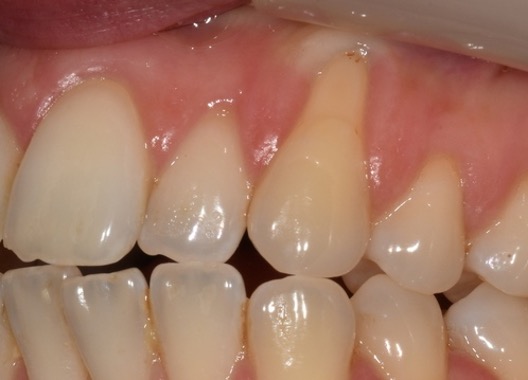

Recession surgery – connective tissue graft

A connective tissue graft is another way to cover recession. This takes a sub-layer of tissue from the palate. The advantage of this is more comfortable healing from the palate and a better colour match to the grafted area.